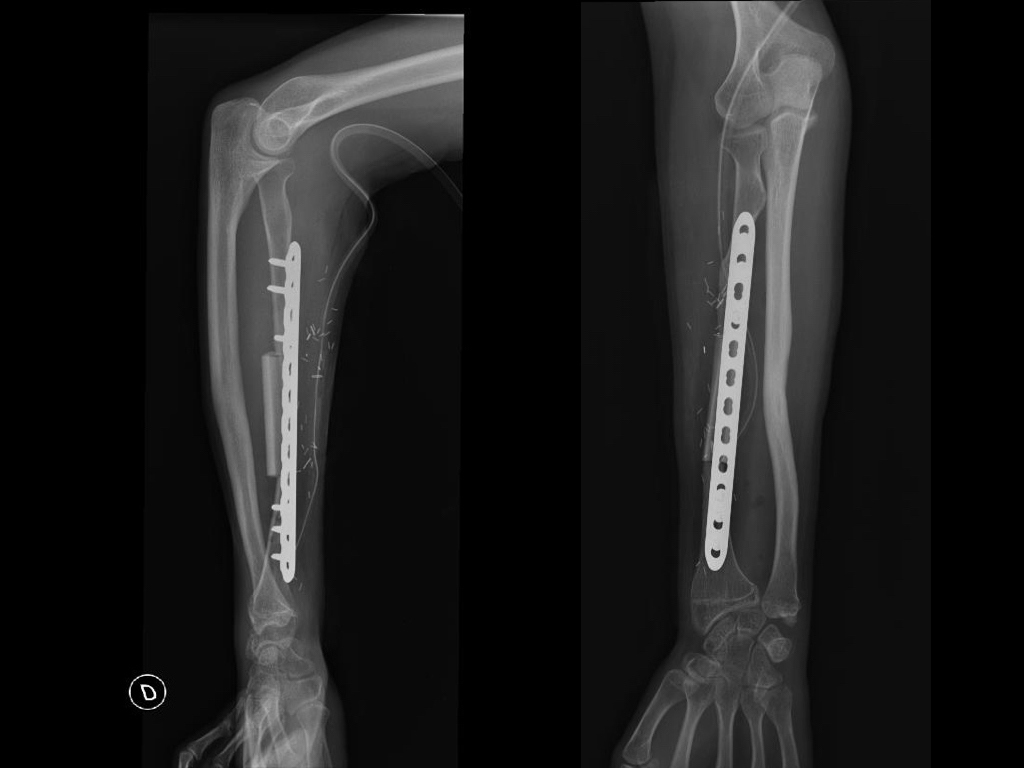

Introducción Los defectos óseos mayores a 6 cm en los huesos largos resultan en un problema difícil a reconstruir del miembro superior. Entre las opciones se encuentran: el injerto óseo alogénico, la utilización de la técnica de Masquelet y el injerto vascularizado de peroné. El peroné vascularizado se ha convertido en el principal método de reconstrucción por sus ventajas biológicas. El objetivo del presente estudio fue evaluar la tasa y el tiempo de consolidación ósea y las complicaciones asociadas en una serie continua de pacientes. Material y MétodosSe realizó una revisión del registro para identificar a todos los pacientes que se sometieron a una reconstrucción con peroné vascularizado durante un periodo de 5 años. Se incluyeron a todos los pacientes que fueron tratados por defectos mayores de 6cm en miembro superior y se excluyeron aquellos en que la reconstrucción se llevó a cabo en el miembro inferior o como técnica asociada para aumentación de la estabilidad en artrodesis de hombro. Se analizaron variables preoperatorias, intraoperatorias y postoperatorias inmediatas y alejadas. Resultados Durante el periodo de evaluación, 18 pacientes fueron sometidos a cirugías reconstructivas con IVP. Seis pacientes (4 hombres/2 mujeres) cumplían con los criterios de inclusión. La edad promedio fue de 47 años (rango 16 a 66 años). En promedio, los pacientes tenían 3 cirugías previas (rango 1 a 4). El tiempo transcurrido entre el trauma inicial y la cirugía reconstructiva varió de 2 a 21 años (promedio 7 años). Las causas del defecto fueron la secuela postraumática (pseudoartrosis) en cinco pacientes y la enfermedad oncológica en un paciente con diagnóstico de Tumor de Células Gigantes. Los segmentos óseos involucrados fueron el húmero (tres pacientes), radio (dos), y cubito (uno). El defecto óseo promedio fue de 10 cm (rango 6 a 15 cm). En cuatro casos se utilizó un injerto osteocutáneo de peroné y un caso sin colgajo fasciocutáneo asociado. En todos los casos, se utilizaron placas bloqueadas como método de fijación del injerto. El tiempo de seguimiento promedio fue de 17 meses (rango de 5 a 40 meses). La consolidación ósea fue lograda en todos los casos. La consolidación ósea llevó promedio de consolidación ósea fue de 16 semanas (rango de 8 a 22 semanas). Dos pacientes sufrieron complicaciones posoperatorias. Un paciente sufrió una exposición del material de osteosíntesis. Otro paciente evolucionó con aflojamiento del material de osteosíntesis. Ninguno de los pacientes presentó complicaciones o secuelas funcionales en la zona dadora. Conclusión El injerto óseo vascularizado de peroné es una opción válida para el tratamiento quirúrgico reconstructivo de defectos óseos segmentarios mayores a 6cm en el miembro superior con una tasa alta de consolidación, aún en casos con múltiples cirugías previas o con larga evolución de la lesión. Los detalles técnicos previenen las complicaciones en la zona dadora.Descargas